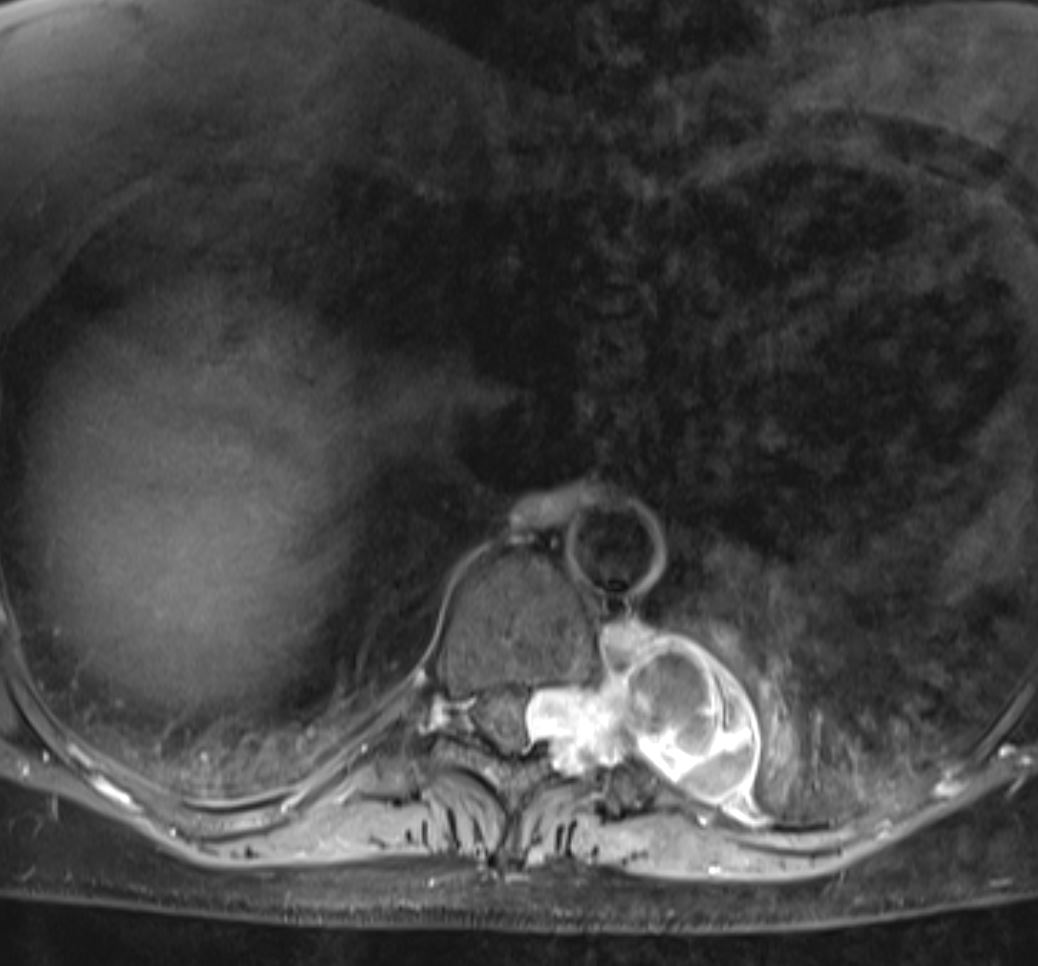

Θωρακικό Σβάννωμα Θ9/Θ10